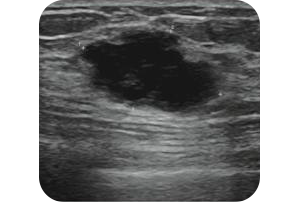

유방암초음파.png 3cm짜리는 대충 이렇게 생겼다 @차움건진센터 홈페이지

이번 문제는 주관식으로, 오답률이 가장 높았다.

왼쪽 가슴에 위치한 암 덩어리는 2개로 정답은 각각 3센티, 1센티 길이다.